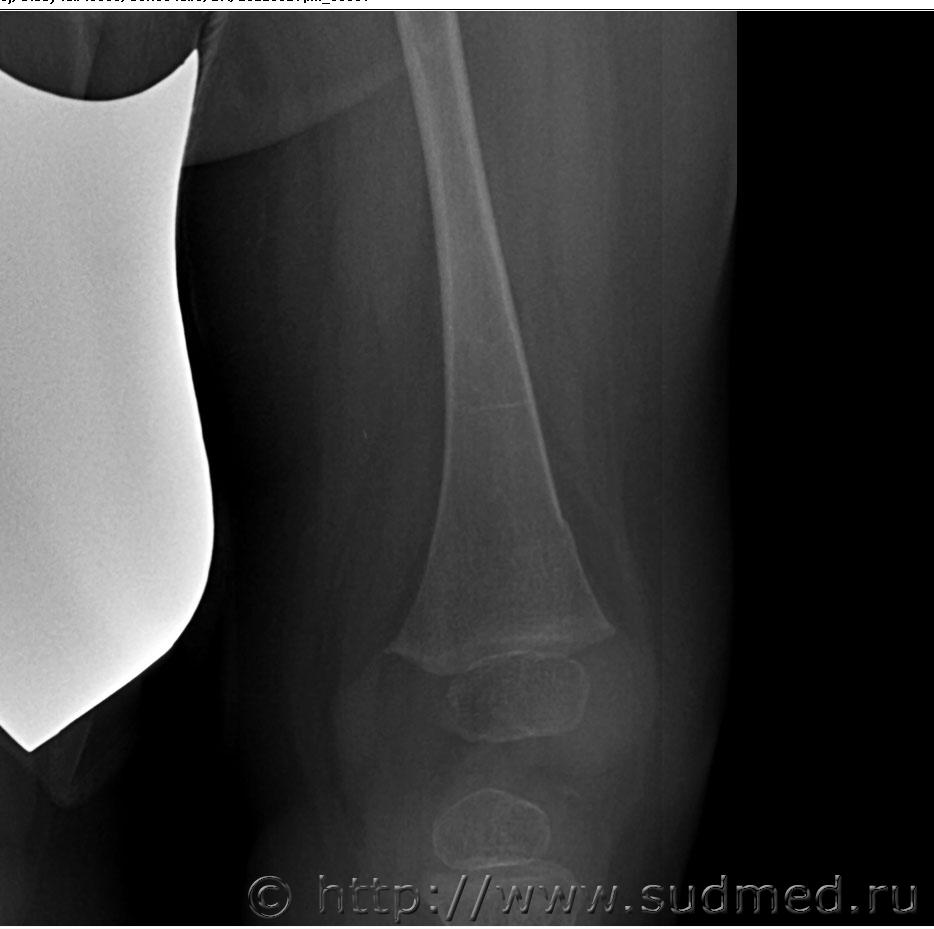

При обращении в травмпункт нижней трети правого бедра и коленного сустава - отек мягких тканей, болезненность при пальпации (ребенок плачет). На момент первичной экспертизы при осмотре бедро в гипсовой лонгете.

Честно говоря, какого -либо уплотнения губчатого вещества я тоже не вижу, возможно Вы правы по поводу отторжения надкостницы. Но две консультации рентгенологов указывают на перелом. Думаю нужна консультация снимков детским травматологом-ортопедом с привлечением рентгенолога.

Противоречивые сведения. Если разные рентгенологи видят разное, то вы правы - нужна ещё консультация.

Впрочем, в нижней трети правого бедра край тени кости тоже не вполне идеально ровный.

Кроме того, даже если допустить, что сил у массажистки предостаточно для причинения вколоченного перелома бедра, то, как я предполагал бы, он должен сопровождаться более грубыми повреждениями мягких тканей.

Способ съёмки, при котором нижняя часть левой голени чуть ли не на 180° супинируется относительно верхней части руками удерживающего, - считаю варварским.